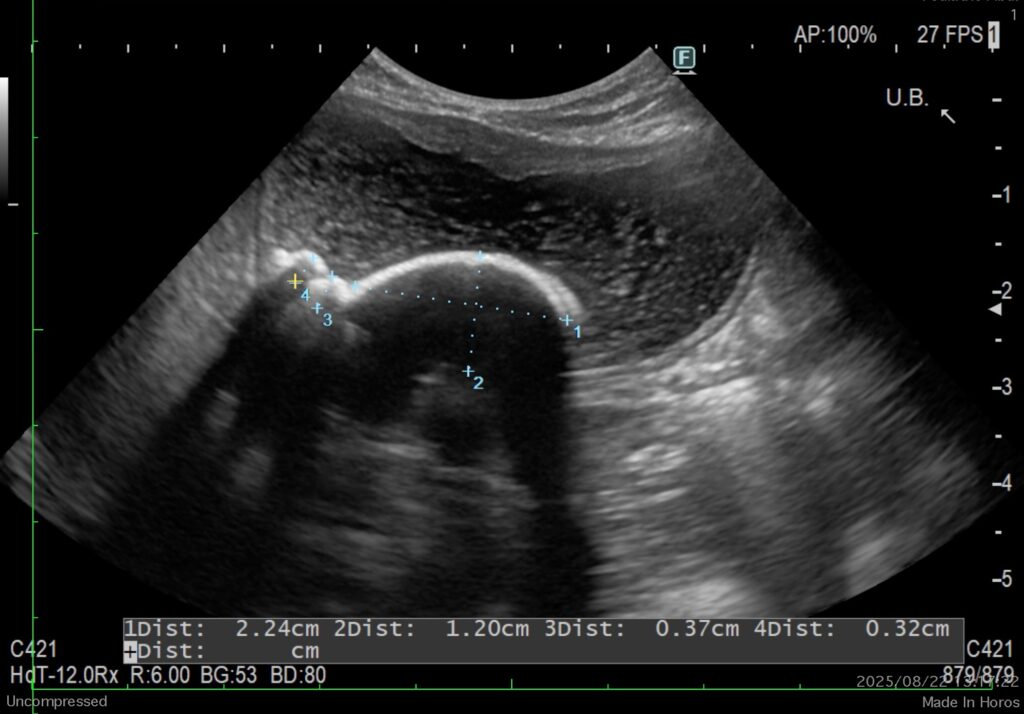

超音波検査で子宮内拡張所見あり(内容物の混濁)、膀胱内に3cm大の結石(他砂粒状の石も多量)。